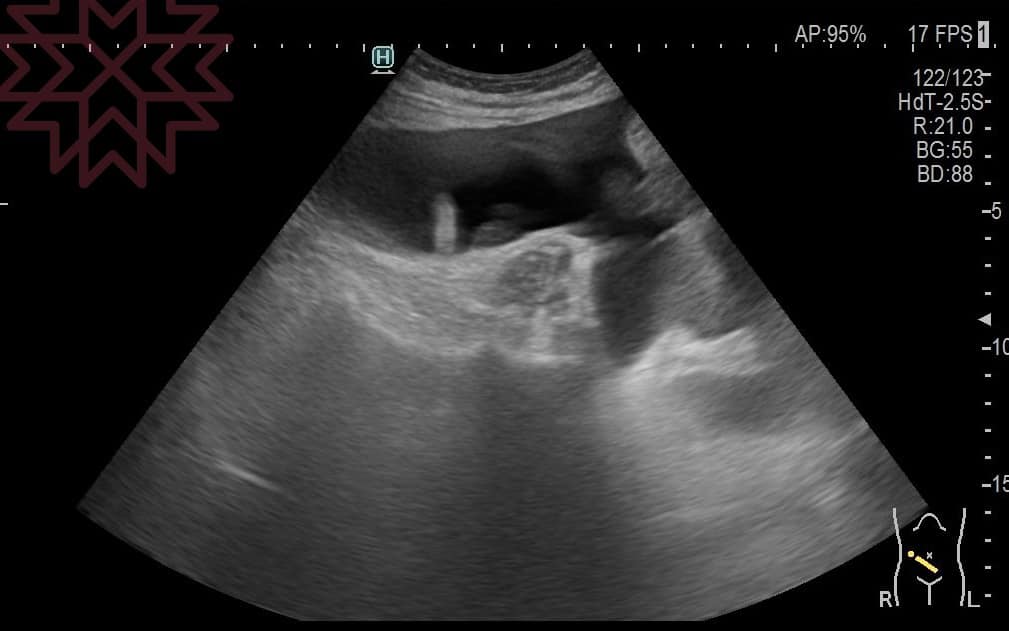

林相宏指出,女子驚覺有異,結果超音波一照,全肚子都是癌症產生的「腹水」,切片確診胰臟癌末期,「這時要如何讓腹水消除、肚子不要發脹呢?我只能說已經腹水難收。」

翻攝自臉書 (胰臟醫師 林相宏 禾馨民權內科診所)